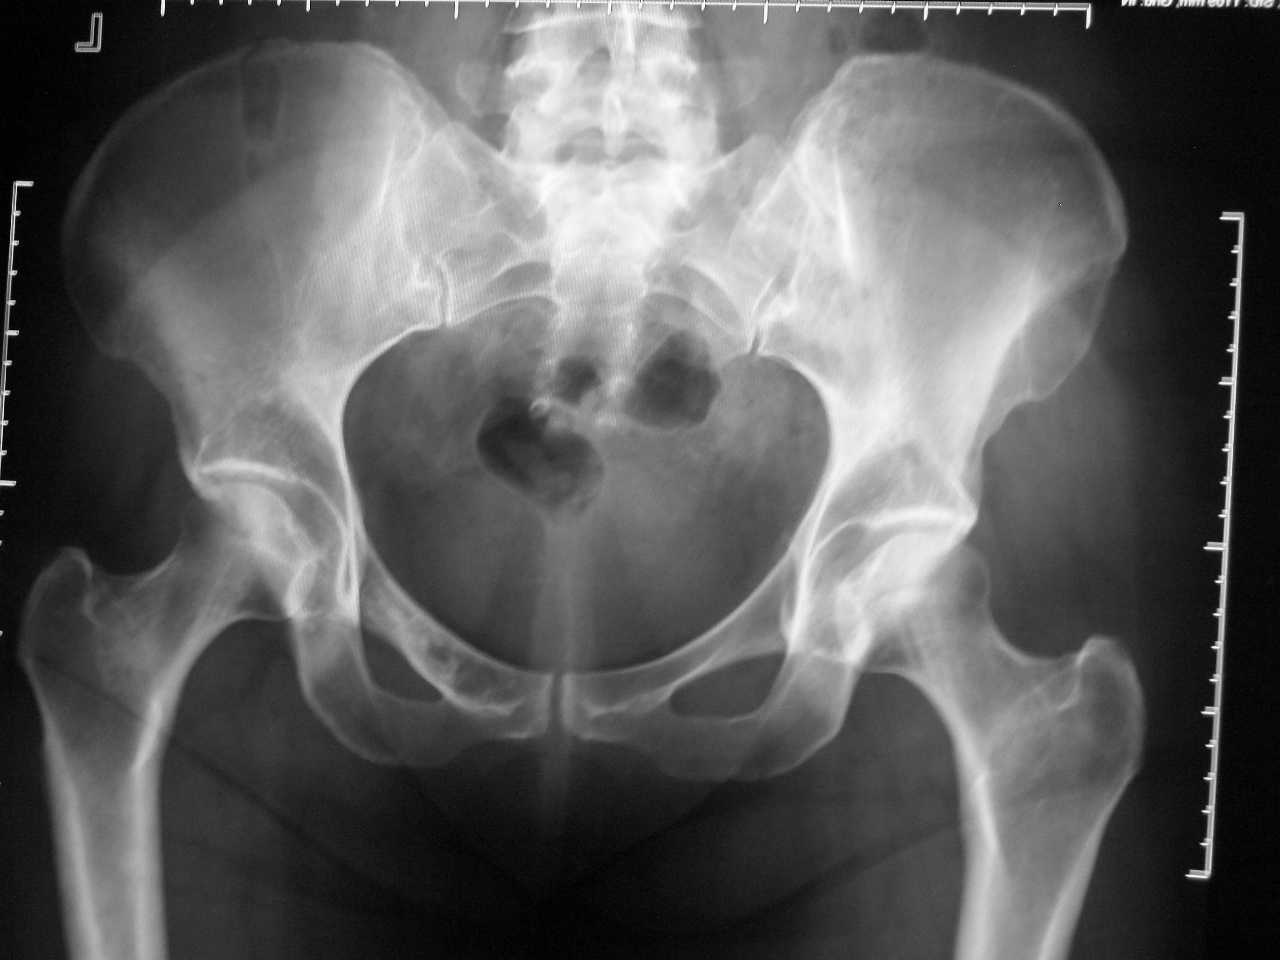

Перелом крестца и копчика

Мнения по поводу приложенного снимка разделились,

а что вы скажете ,уважаемые коллеги?